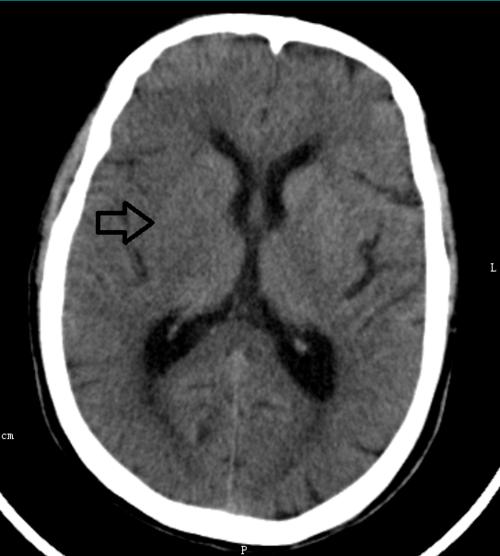

超急性期大面积脑梗死 ct 平扫表现

头部ct请大家看看

脑ct片子求解?

脑部ct怎么看图解

脑ct图片讲解

新手看脑部ct片图解

脑梗塞ct图片解说图